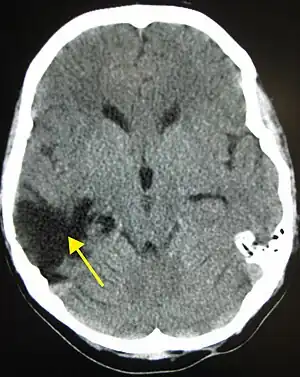

| A CT of the head years after a traumatic brain injury showing an empty space where the damage occurred, marked by the arrow | |

There are several imaging techniques that can aid in diagnosing and assessing the extent of brain damage, such as computed tomography (CT) scan, magnetic resonance imaging (MRI), diffusion tensor imaging (DTI) magnetic resonance spectroscopy (MRS), positron emission tomography (PET), and single-photon emission tomography (SPECT). CT scans and MRI are the two techniques widely used and are most effective. CT scans can show brain bleeds, fractures of the skull, fluid build up in the brain that will lead to increased cranial pressure. MRI is able to better to detect smaller injuries, detect damage within the brain, diffuse axonal injury, injuries to the brainstem, posterior fossa, and subtemporal and subfrontal regions. However, patients with pacemakers, metallic implants, or other metal within their bodies are unable to have an MRI done. Typically the other imaging techniques are not used in a clinical setting because of the cost, lack of availability.[36]